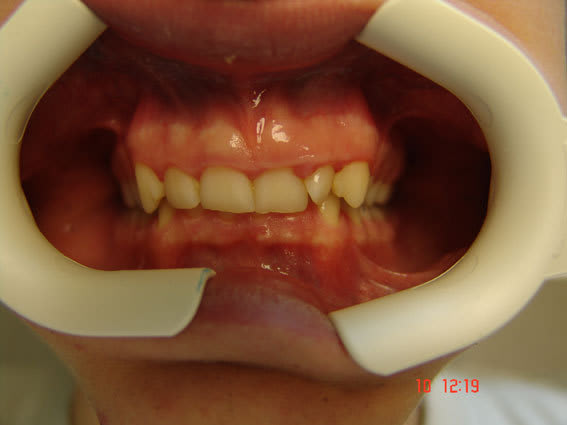

Au total: supraclusion incisive, déviation point interincisif inf vers la droite, décalage entre les bords libres des incisives / canines et le plan occlusal des molaires prémolaires, déglutition dents serrées. Pas de caries. Paro+/-. Hypotonie droite (cfr épaules).

sur la premiere photo il semble que on a un quasi articulé inversé au niveau de la 45, la 11 est plus usée que la 21 mais la 13 est quasi intacte (trés longue mais normal à 14 ans)et donc je dirais qu'il mastique à droite et seulement à droite.

Effectivement, il fonctionne à droite.

Est-il possible que la mastication unilatérale puisse à elle seule amener la déviation?

Et si cette mastication est unilatérale droite, pourquoi s'est-elle installée, alors qu'il n'y a pas eu de problème carieux justifiant un réflexe d'évitement?

Et pourquoi la supraclusion? Serait-elle en rapport avec la mastication unilatérale. Pourquoi ces deux "mouvements"?